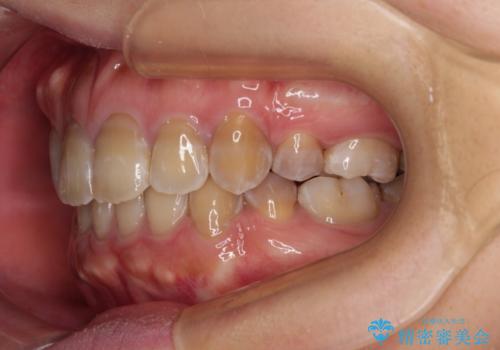

- 口元の突出感を気にして来院された患者様です。

上下前歯が著しく前突している状態であったので、上下左右の第1小臼歯4本を抜歯し、ワイヤー装置にて矯正治療を行うこととしました。

舌の突出癖により、前突になったと考えられたため、舌のトレーニングをしっかりと行うよう指導しました。

4本の歯を抜歯したことで、飛び出していた口元が引っ込み、横顔が大きく改善されました。